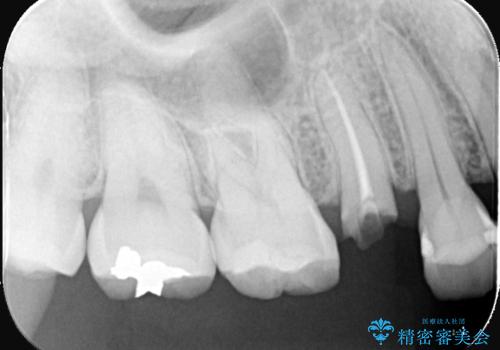

- 患者様は「歯が取れたこと」を主訴に来院されました。

診査の結果、土台ごと脱離しており、歯質の残存量も少ない状態でした。

患者様は歯の保存を強く希望されたため、保存可能な範囲で丁寧に形成を行い、フェルール(歯冠縁下の歯質保持)を確保することを優先しました。